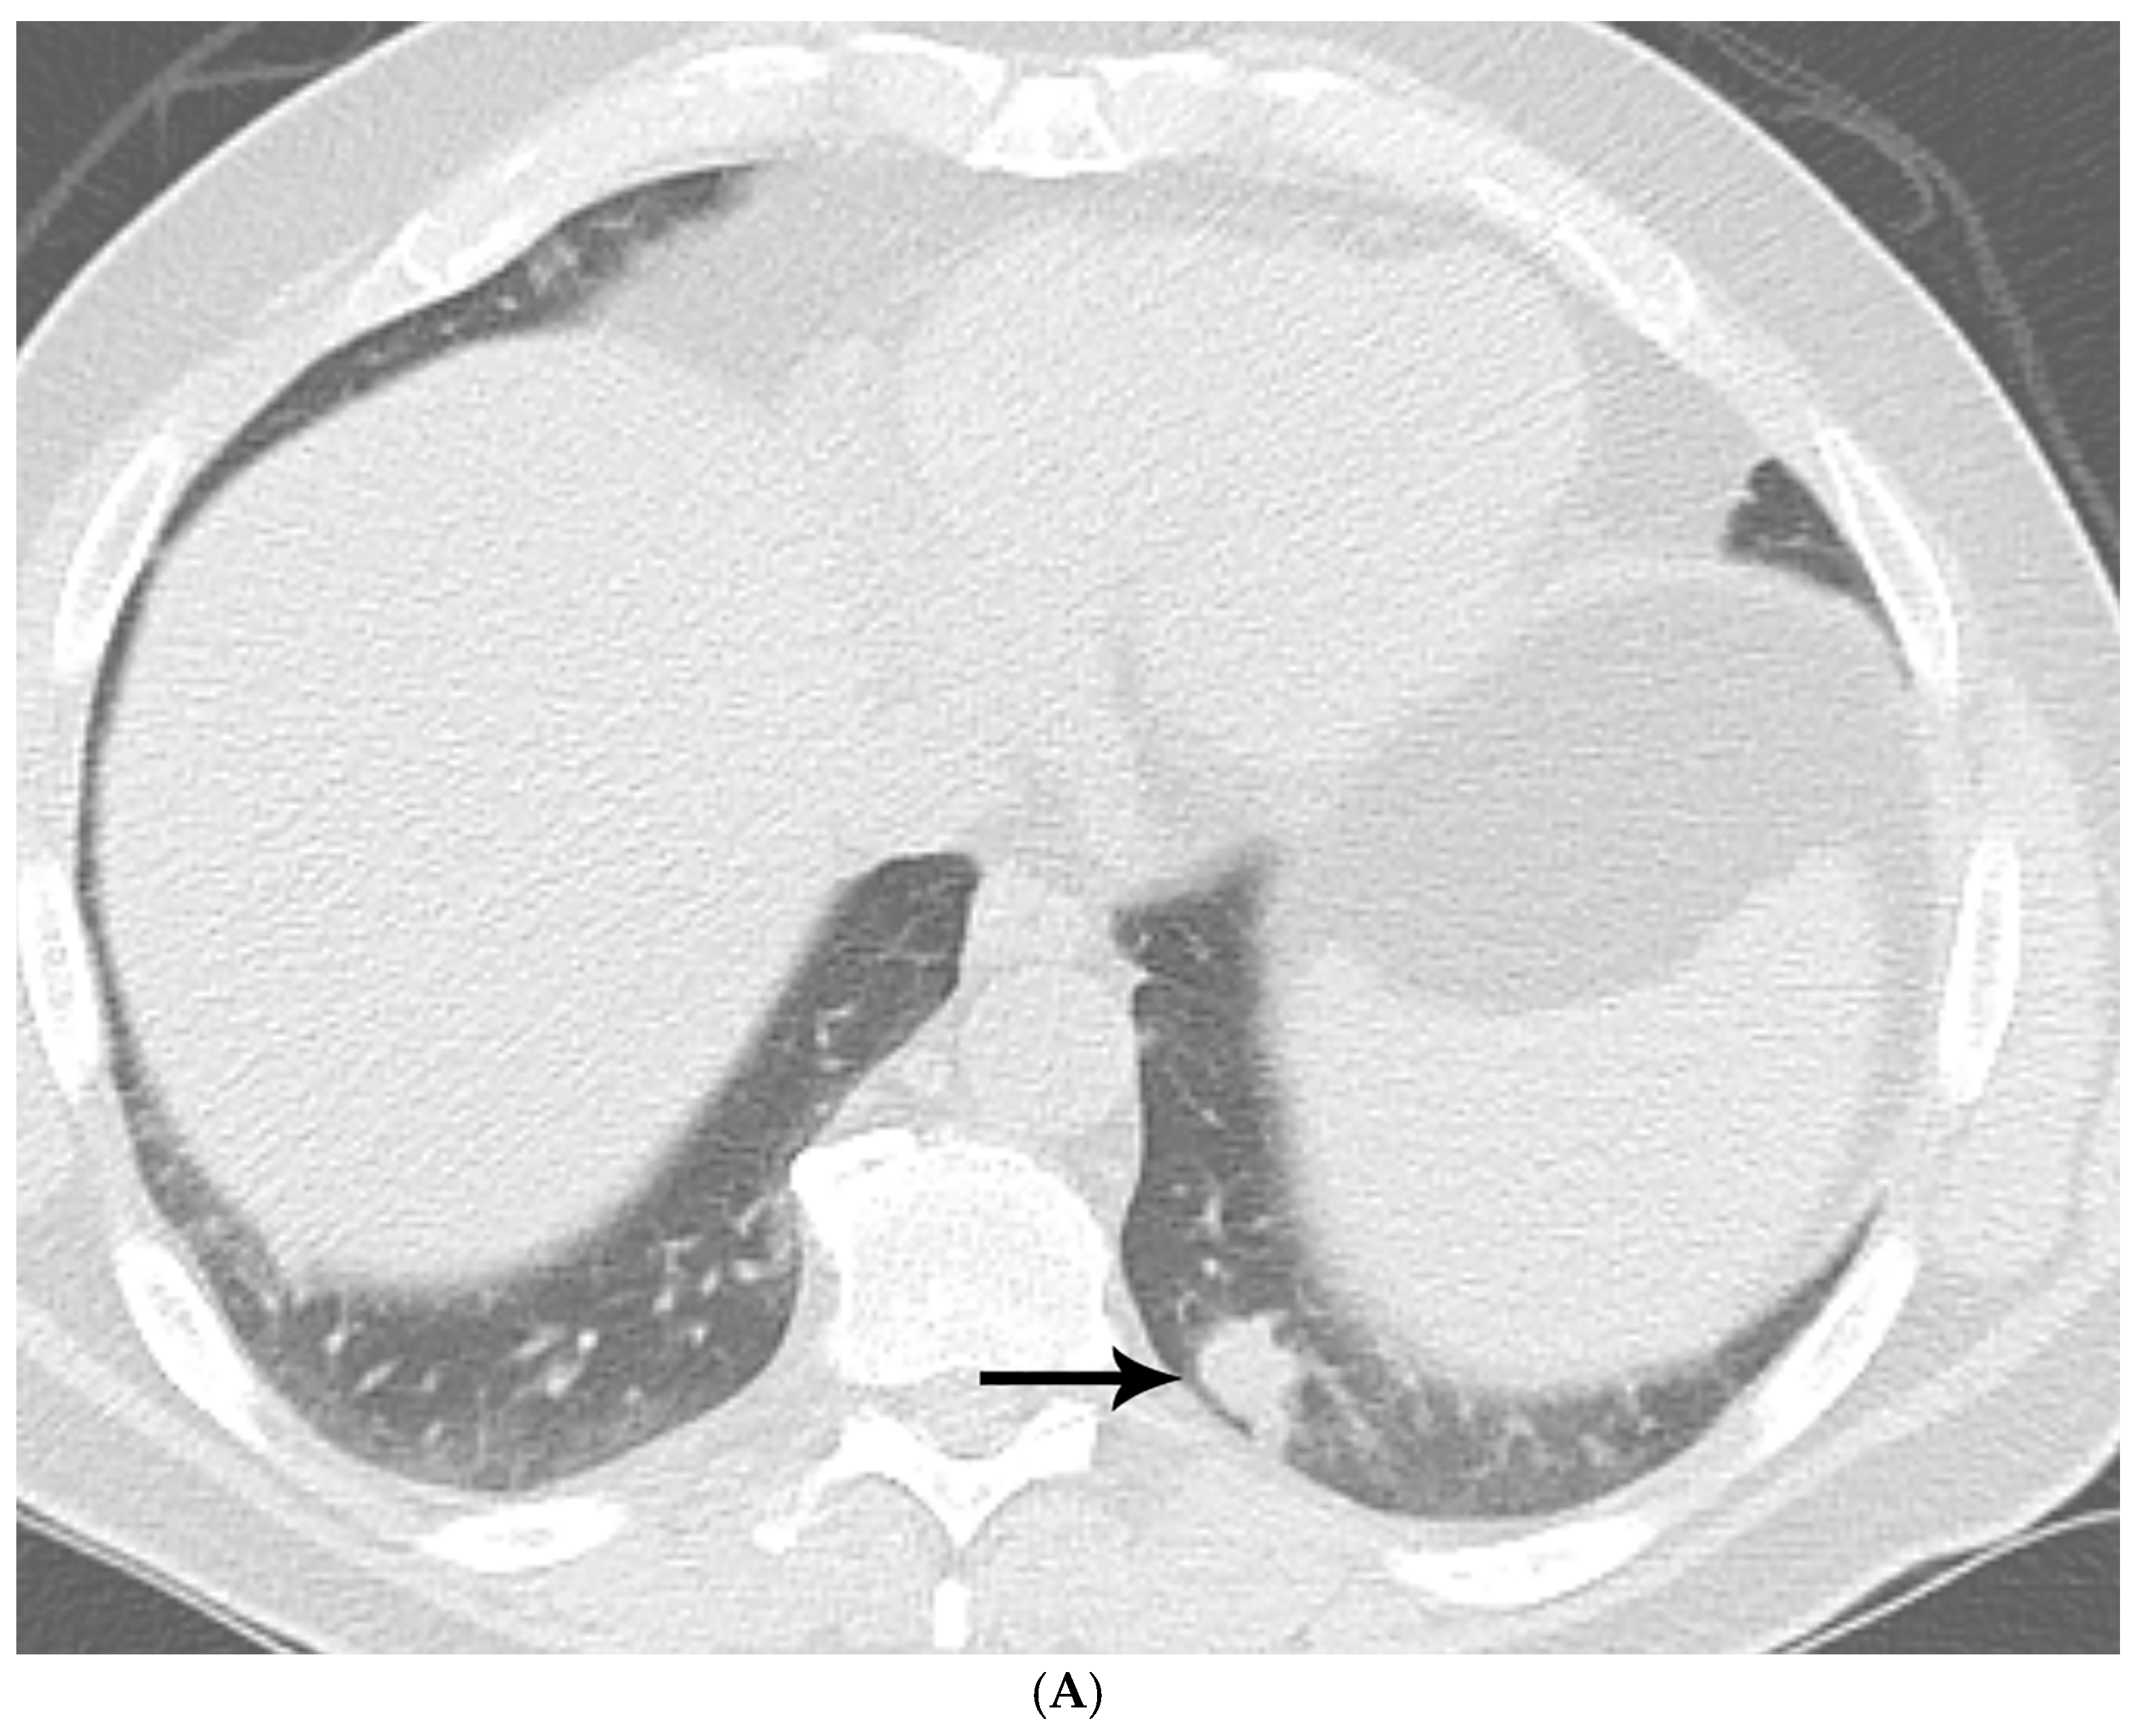

- By imaging, the distinction between an infectious process and neoplasia remains a diagnostic challenge.